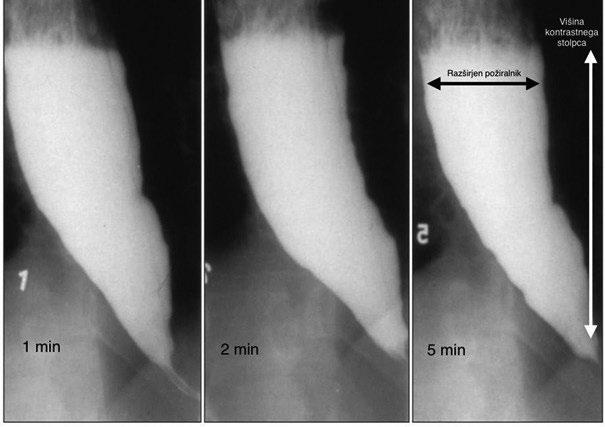

Kontrastna rentgenska preiskava požiralnika s kontrastnim sredstvom je uveljavljena metoda pri obravnavi ahalazije. Značilne radiološke spremembe vključujejo postopno zoženje distalnega dela požiralnika, dilatacijo požiralnika nad ezofagogastričnim prehodom, odsotnost primarne peristaltike in zastajanje kontrastnega sredstva nad LES. Te spremembe v zgodnjih fazah bolezni niso vedno prisotne, zato normalen izvid ne izključuje ahalazije (2). Za natančnejšo oceno prehoda bolusa skozi ezofagogastrični prehod se uporablja tudi test z barijevim kontrastom. Preiskava vključuje zaužitje večje količine kontrastnega sredstva, ki vsebuje barij, nato pa se serijske rentgenske slike posnamejo po 1, 2 in 5 minutah. Na posnetkih se meri višina kontrastnega sredstva oziroma tako imenovani kontrastni stolpec, ki predstavlja količino kontrasta, zadržanega v požiralniku zaradi motenega praznjenja skozi ezofagogastrični prehod. Večja višina in počasnejše zmanjševanje kontrastnega stolpca kažeta na izrazitejšo obstrukcijo in slabšo funkcionalno prehodnost požiralnika. Metoda omogoča kvantitativno spremljanje stopnje zadrževanja vsebine v požiralniku ter je posebej uporabna pri ocenjevanju uspešnosti zdravljenja in zgodnjem odkrivanju ponovitve bolezni (1, 2). Slika 3 prikazuje test z barijevim kontrastom pri bolniku z ahalazijo. Na zaporednih rentgenskih posnetkih, opravljenih 1, 2 in 5 minut po zaužitju kontrastnega sredstva, je vidno izrazito zadrževanje kontrasta v požiralniku. Ker tudi po 5 minutah ne pride do bistvenega zmanjšanja višine kontrastnega stolpca, to kaže na moteno praznjenje požiralnika, omejen prehod skozi ezofagogastrični prehod in odsotnost učinkovite peristaltike (4).